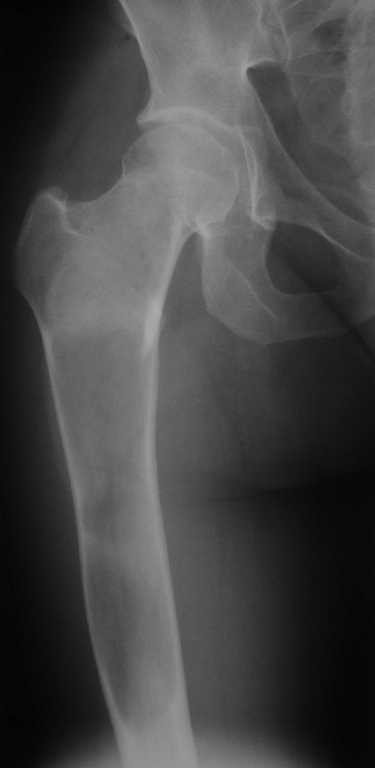

Движения в правом тазобедренном суставе в полном объёме, практически безболезненные. По результатамx-ray диагностики выявлен патологический очаг, занимающий весь проксимальный отдел и 2/3 диафиза правой бедренной кости. Другие трубчатые кости верхних и нижних конечностей - без очагов поражения.

К тому же на снимке виден на мой взгляд обширный литический очаг в средней и верхней трети бедренной кости центрального расположения с не четкими границами с утоньшением кортекса и периостальной реакцией вверхней трети латерально.

Заранее извиняюсь за плохое знание медицинской терминологии на русском, так как получил медицинское образование в США. Для начала, я бы сделал снимки всего бедра. На данных снимках, не видно нижней границы опухоли. КТ и МРТ всего бедра следует сделать. Фиброзная дисплазия вызывает боль в четырёх случаях:

1. трансформация в саркому. Это крайне редкое явление, но,разумеется, самое опасное.

2. микротрещины ослабленной кости, что бывает при фиброзной дисплазии. В этом случае периостальная реакция может быть этим объяснена. К тому же присудствующая периостальная реакция гладкая, как при доброкачественном процессе. Но КТ лучьше покажет её.

3. Трансформация в простую кисту (unicameral bone cyst) с последующими микротрещинами.

4. Трансформация в аневризмальную кисту кости (aneurysmal bone cyst). МРТ поможет вам различить вариант 3 от варианта 4.

P.S. Вариант номер 3 наиболее вероятен в этом случае. Границы опухоли чётко обозначены на фронтальной проекции, так что опухоль скорее всего доброкачественная. Если КТ и МРТ его подтвердят, то интрамедулярный стержень с фиксацией в шейку бедра избавит пациентку от боли.